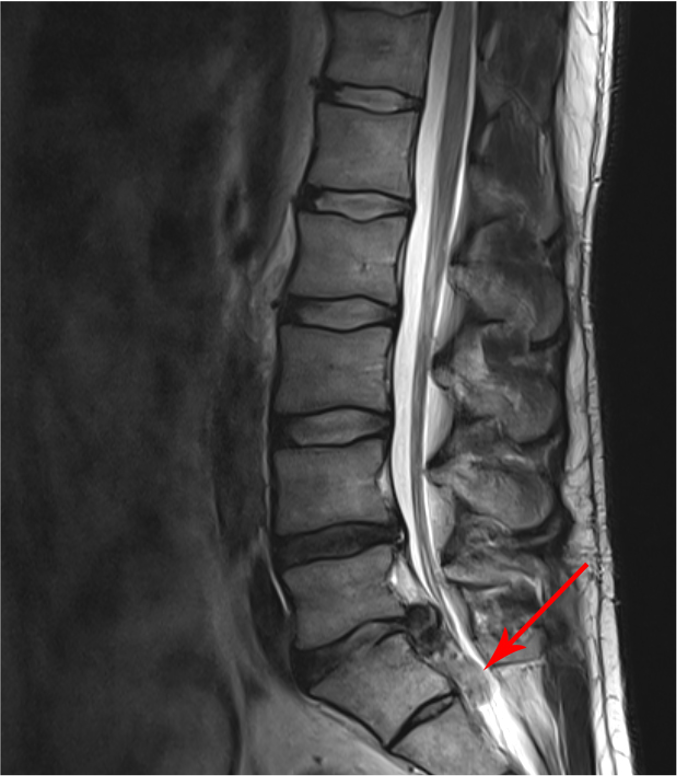

Die MRT-Bilder zeigen einen 78-jährigen Patienten mit Schwäche- und Taubheitsgefühlen in den Beinen, schon nach 20 Meter Gehstrecke.

Das erste Bild zeigt eine Einengung des Spinalkanals in 3 Höhen, das Zweite Bild zeigt den selben Patienten 6 Monate nach seiner OP.

Hier sieht man eine deutlich Entlastung der Nervenfasern. Im Gegensatz zum ersten Bild sind die Fasern nicht mehr gequetscht und zeigen um die Engstellen keine spiralförmige Aufwertung mehr.